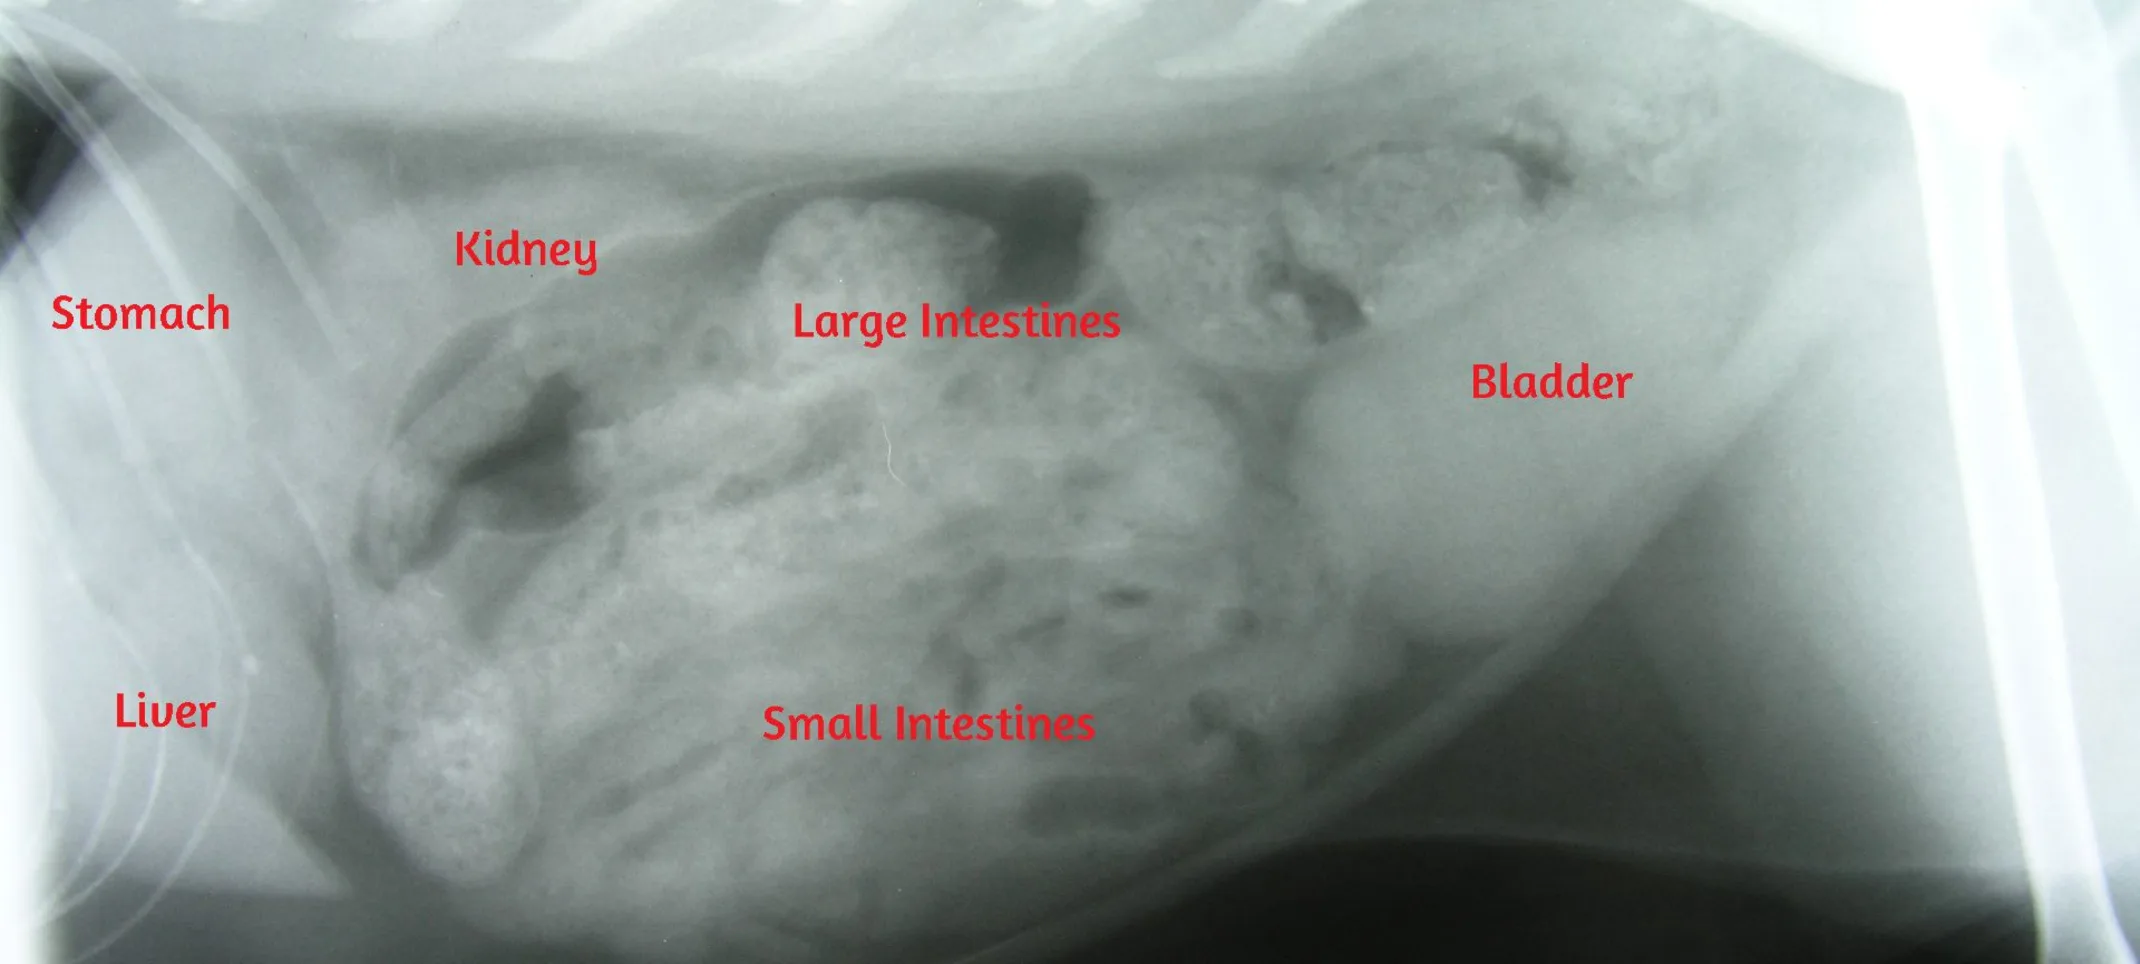

X-ray showing a dog with Bloat (GDV) with the large distended stomach that has twisted and required emergency surgery